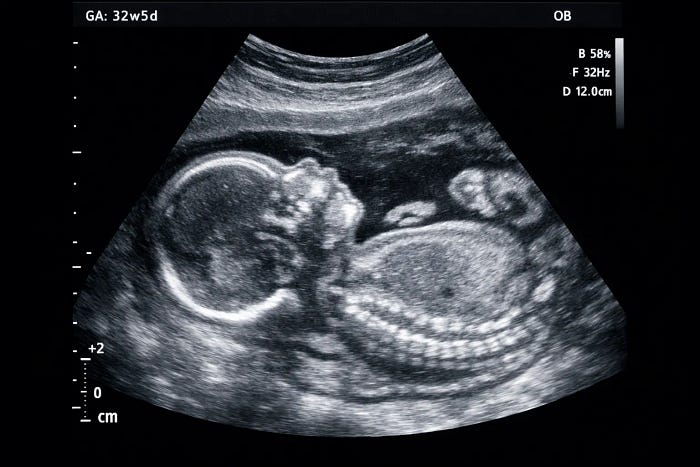

4. Growth and Follow-Up Scans (Later Pregnancy)

Ultrasound pregnancy scans in the later stages are often performed with a referral and recommended based on the individual needs of the expectant mother, her progress, and her health. These scans are usually performed to check the baby’s position, assess placental and fluid levels, and monitor its growth patterns.